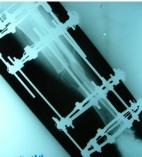

این عمل در مرکز جراحی ولنجک و زیر نظر دکتر حقانی فوق تخصص دست صورت گرفته

تاریخ عمل  پنج شنبه 20 شهریور 1393

شست کوتاه